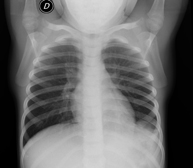

- RX Tòrax

Tècnica que usa els raigs X a través de la qual s'obtenen imatges de la caixa toràcica (cor, pulmó, arcs costal, clavícules, etc.) per al seu estudi. - RX Ester

Tècnica que usa els raigs X a través de la qual s'obtenen imatges dels sins paranasals per al seu estudi. Indicacions: cefalea, tos crònica. - RX Tòrax

Una radiografia de tòrax és una tècnica mitjançant la qual, amb l'ús d'una petita dosi de radiació, s'obté una imatge bidimensional de la caixa toràcica i el seu contingut (pulmons, cor, mediastí, etc. ). És una de les proves mèdiques realitzades més comuna. - RX Abdomen